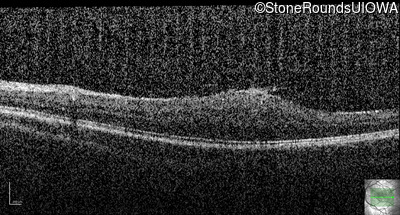

This 9 year old male was noted to have some crossing of his eyes at 2 months of age and the eye exam which followed identified a retinal lesion in the right eye. When he was six years old an epiretinal membrane was noted in his left eye. Two years later it was decided that it was a thin hamartoma in that eye as well. He underwent neuroimaging at age 7 which identified bilateral acoustic neuromas.

| Age at visit: 8 years |

| Age at visit: 10 years |

| Age at visit: 11 years |

| Age at visit: 14 years |